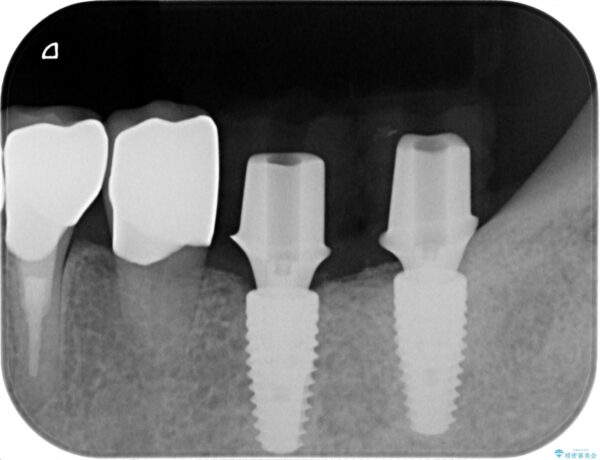

ブリッジの支台となる後方臼歯は清掃性が悪く虫歯が大きくなっていたため、抜去を行いインプラントを用いた治療としました。

治療中

劣化の進んだブリッジの再治療[ 不適合な補綴物による虫歯の再発 ] 治療中画像 劣化の進んだブリッジの再治療[ 不適合な補綴物による虫歯の再発 ] 治療中画像 劣化の進んだブリッジの再治療[ 不適合な補綴物による虫歯の再発 ] 治療中画像